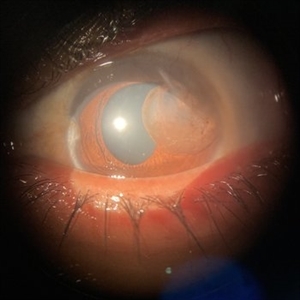

Traumatic Iris Cyst

Diffuse illumination slit lamp image of a 30-year-old female patient with a traumatic iris cyst in left eye.

Photographer: Dr. Akansha Sharma - Retina Foundation, Ahmedabad

Condition/keywords: cyst, iris, trauma